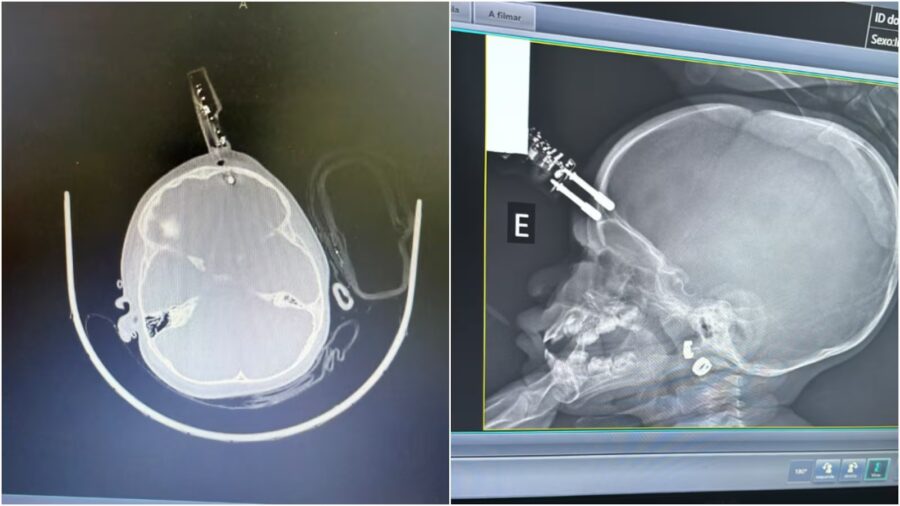

Uma menina de 1 ano e 4 meses sofreu um grave acidente doméstico ao cair da cama e ficar com um pino de carregador de celular cravado na testa, em Divinópolis, a 117 quilômetros de Belo Horizonte. O objeto atingiu o cérebro, e a criança precisou passar por cirurgia de emergência para a retirada.

“Era um carregador de celular comum. Um dos pinos estava cravado, atravessando o crânio na região frontal da criança”, explicou o médico.